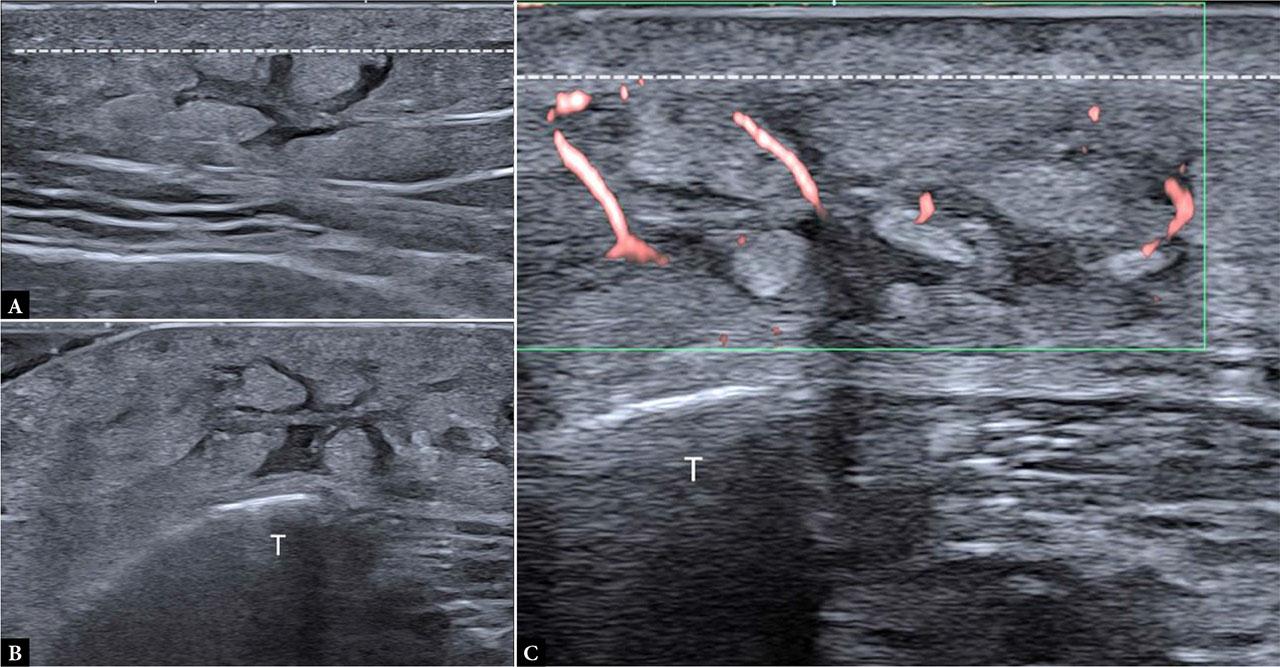

On ultrasound, malignant panniculitis may demonstrate plaque-like areas of cutaneous thickening and mass formation or as ill-defined areas within the subcutaneous fat containing hypoechoic foci on a hyperechoic background, with hypervascularity and a low resistive index on Doppler evaluation(25) (Fig. 7).

Malignant panniculitis: A, B. B-mode and Power Doppler images of a subcutaneous nodule in the posterior aspect of the right arm in a 47-year-old woman with lymphoblastic leukemia, showing a poorly marginated area in the subcutaneous tissue with increased volume and echogenicity, hypoechoic lines, and central and peripheral hyperemia; C, D. B-mode and Power Doppler images of a subcutaneous nodule in the posterior aspect of the right arm in a 41-year-old man with panniculitis-like T-cell lymphoma, showing a mixed panniculitis pattern involving the DSAT with chaotic vascular signals; the SSAT and dermis are spared

Among these entities, the most characteristic example is panniculitis-like T-cell lymphoma, a rare, indolent type of cutaneous lymphoma with primary origin in the SAT. It is characterized by predominant infiltration of subcutaneous adipose tissue with sparing of the dermis and epidermis. This subtype is especially relevant because patients typically present clinically with multiple palpable subcutaneous nodules without lymphadenopathy and are often misdiagnosed as having inflammatory panniculitis(26).